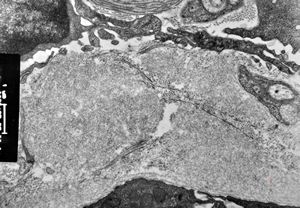

F,45y. | jejunum … amyloidosis

M,60y. | jejunum - amyloidosis